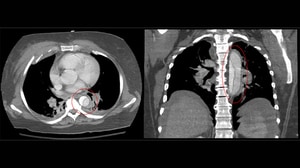

Aortic Dissection: A Double-Barreled ThreatSudden onset tearing chest pain can be the initial presentation of an aortic dissection. A small tear can quickly split the aortic wall, which may be fatal even with prompt treatment.